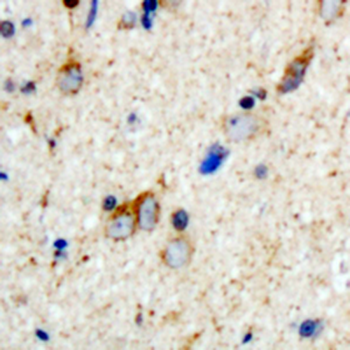

Immunohistochemical analysis of Aquaporin 2 (pS256) staining in human brain formalin fixed paraffin embedded tissue section. The section was pre-treated using heat mediated antigen retrieval with sodium citrate buffer (pH6.0). The section was then incubated with the antibody at room temperature and detected using an HRP conjugated compact polymer system. DAB was used as the chromogen. The section was then counterstained with haematoxylin and mounted with DPX.